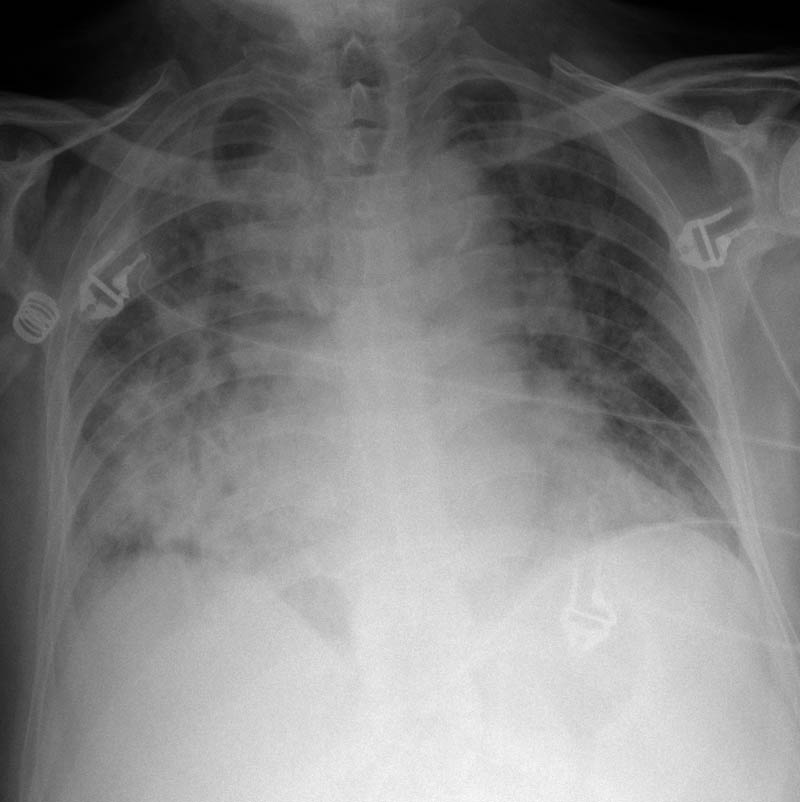

MO Distres respiratorio del adulto por trauma.

MO Distrés respiratorio del adulto